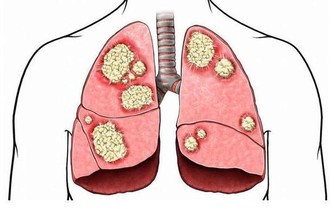

因為肚臍的皮膚非常薄,摳肚臍會導致皮膚紅腫或者發炎,

一旦感染會順著肝圓韌帶一路到達肝臟,從而引發內臟感染!